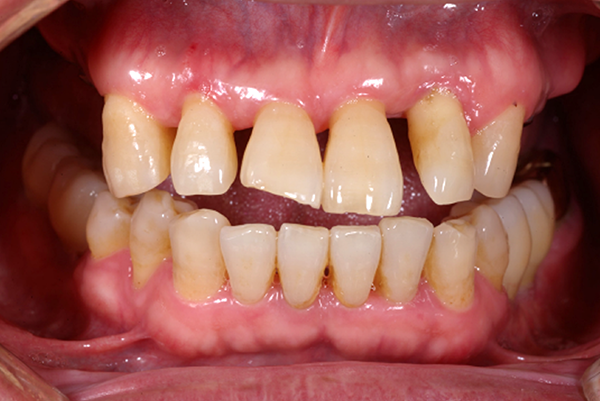

잇몸이 붉지 않고, 연분홍빛을 띠며 단단하게 치아를 감싸고 있습니다. 엑스레이 에서는 치아 뿌리를 따라 잇몸뼈가 치아 경계선 바로 아래까지 촘촘하게 유지되 고 있습니다.

겉으로 보기에도 치석과 염증이 심하며, 잇몸이 심하게 붓고 내려앉아 있습니다. 엑스레이에서는 뿌리의 절반 이상이 드러날 정도로 잇몸뼈가 심각하게 소실되어 있습니다.

잇몸이 붉지 않고, 연분홍빛을 띠며 단단하게 치아를 감싸고 있습니다. 엑스레이에서는 치아 뿌리를 따라 잇몸뼈가 치아 경계선 바로 아래까지 촘촘하게 유지되고 있습니다.